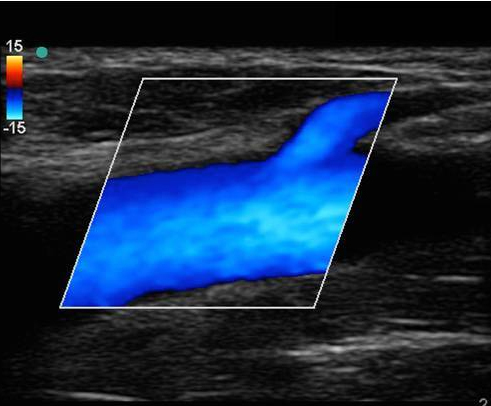

Imagen en color de trombosis venosa profunda en la porción proximal de la vena femoral